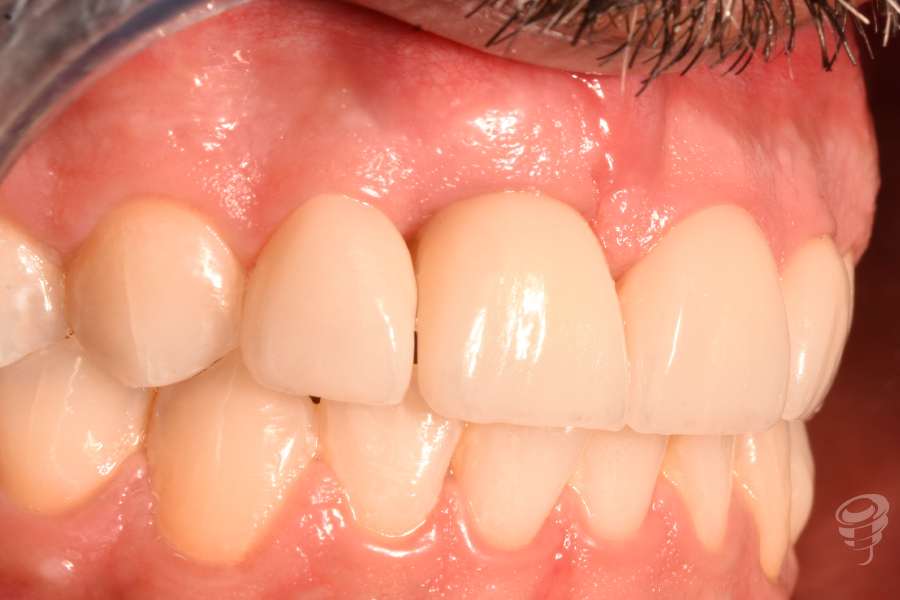

Resultado

Revisión a los 24 meses

Figura 50

Figura 51

Figura 52

Figura 53

- Las carillas de cerámica corrigieron pequeñas discrepancias de forma y color en 12 y 21, logrando una transición imperceptible con la corona implanto-soportada.